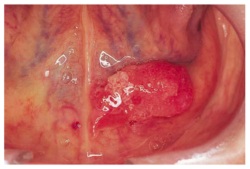

What Some Oral (Mouth) May Cancers Look Like

A shallow

ulcer on the lower lip

A speckled ulcer

Tongue cancer

A red

patch under the tongue

These photographs are not meant to scare you. Just to remind you about what some oral cancers may look like. Get a doc-check if anything at all doesn’t seem right to you.